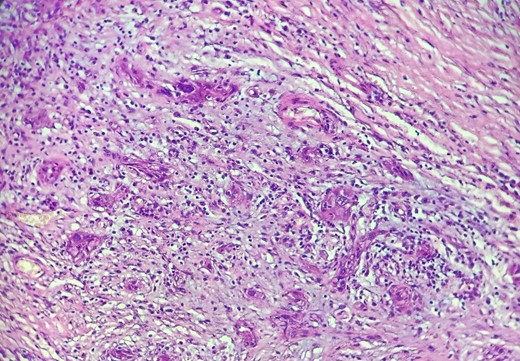

Mr. A. is a 65-year-old hypertensive patient presenting with acute epigastric pain associated with abdominal bloating. Biological settings showed amylasemia at 450 IU/L and lipasemia at 525 IU/L. Abdominal CT scan revealed heterogenous poorly defined mass in the pancreatic head with low enhancement (Figs 1 and 2). The CA 19–9 assay was 280 IU/L. Cephalic duodenopancreatectomy was performed. Histological examination of the operative specimen revealed a solid, trabecular, undifferentiated carcinomatous process (Fig. 3) expressing markers (CK(AE1-AE3) and p40) (Fig. 4), confirming the diagnosis of primary squamous cell carcinoma of the pancreas. The extension study showed no secondary localization.

HE section: The tumor cells are so poorly differentiated that it is difficult to tell what the cell of origin is. The cells are discohesive with bizarre looking nuclei (×400).